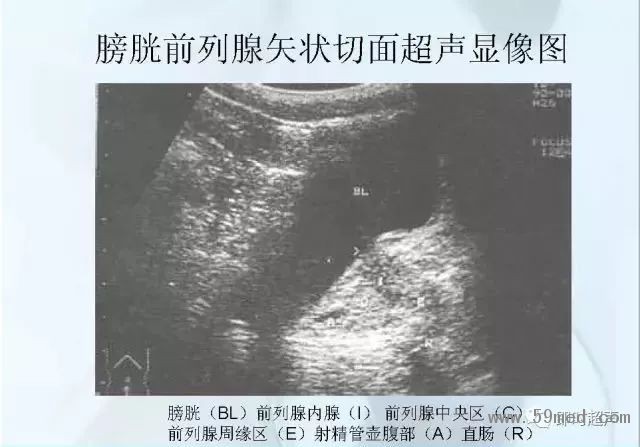

新聞中心 收藏!正常B超解剖圖譜,超實用!